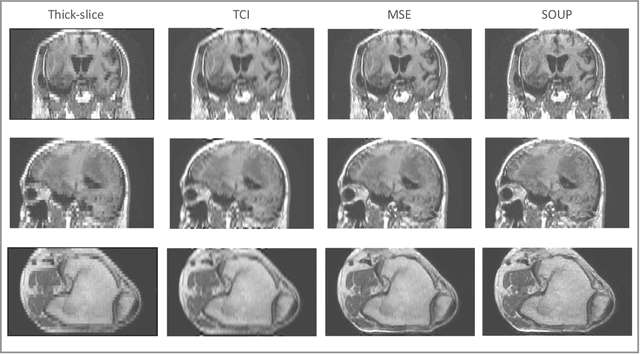

Abstract:There is a growing demand for high-resolution (HR) medical images in both the clinical and research applications. Image quality is inevitably traded off with the acquisition time for better patient comfort, lower examination costs, dose, and fewer motion-induced artifacts. For many image-based tasks, increasing the apparent resolution in the perpendicular plane to produce multi-planar reformats or 3D images is commonly used. Single image super-resolution (SR) is a promising technique to provide HR images based on unsupervised learning to increase resolution of a 2D image, but there are few reports on 3D SR. Further, perceptual loss is proposed in the literature to better capture the textual details and edges than using pixel-wise loss functions, by comparing the semantic distances in the high-dimensional feature space of a pre-trained 2D network (e.g., VGG). However, it is not clear how one should generalize it to 3D medical images, and the attendant implications are still unclear. In this paper, we propose a framework called SOUP-GAN: Super-resolution Optimized Using Perceptual-tuned Generative Adversarial Network (GAN), in order to produce thinner slice (e.g., high resolution in the 'Z' plane) medical images with anti-aliasing and deblurring. The proposed method outperforms other conventional resolution-enhancement methods and previous SR work on medical images upon both qualitative and quantitative comparisons. Specifically, we examine the model in terms of its generalization for various SR ratios and imaging modalities. By addressing those limitations, our model shows promise as a novel 3D SR interpolation technique, providing potential applications in both clinical and research settings.